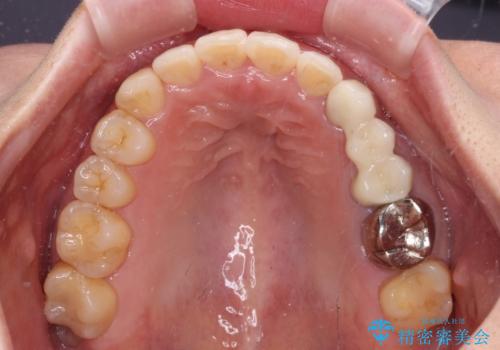

矯正治療後には切断したブリッジをオールセラミックブリッジに置き換えることとしました。

矯正治療中に上下前歯が接触しない時期があり、咬み合わせ改善のために期間がかかるのではないかと懸念されましたが、結果的には補綴治療も含めて1年以内の短期間で終えることができました。